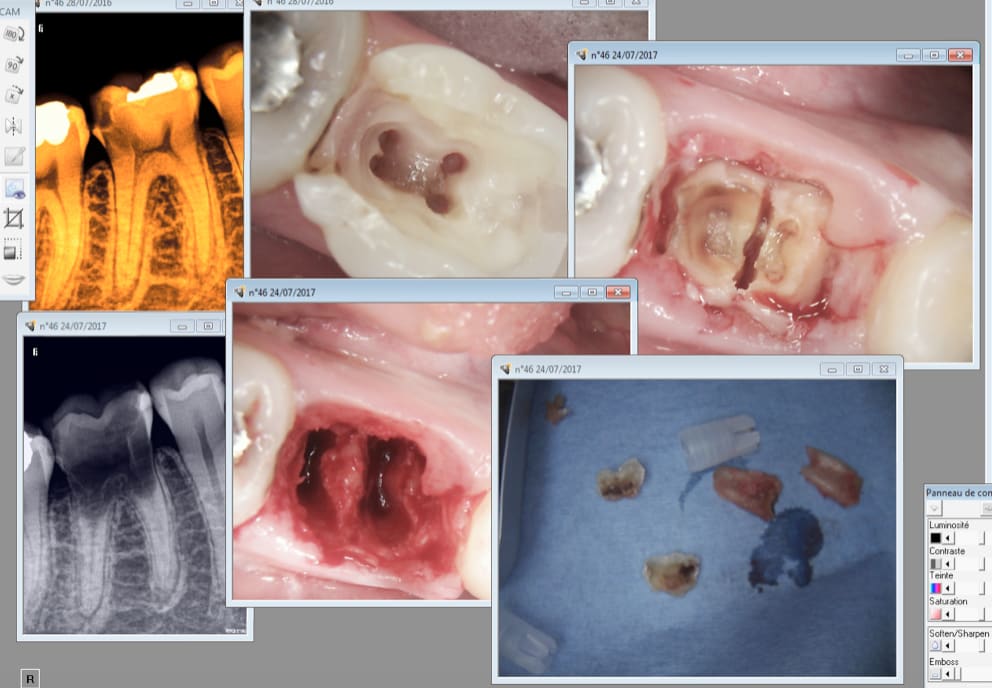

Je devance la réflexion de casa qui pense que je sors mes R25 pour un oui ou our un non par un exemple qui illustre la vie quotidienne au cabinet. Cas extrême, mais relativement fréquent, qui illustre la parfaite dé responsabilisation des patients en France qui ne consultent en général qu'à l'occasion de signes d'appels hormis ceux qui on besoin d'une attestation. Attestation en vue d'une intervention chirurgicale ou attestation de bonne santé buccodentaire par exemple pour les militaires. On voit aussi des femmes enceintes depuis l'idée lumineuse du BBD qui tombe pile poil au moment propice pour faire des soins. -)

Donc patiente vue en urgence pour une pulpite sur 46 il y a un an, ouverture chambre . Le 10 juillet de cette année consulte en urgence pour une pulpite mais sur la 37. Je la prends ouverture chambre et RDV aujourd'hui pour l'endo et miracle ! elle est venue. J'en ai profité pour virer la 46 dans la foulée. -) J'y ai collé un IRM ( on ne sait jamais lol !) Et peut etre qu'un jour on aura l'occasion de faire une couronne et de soigner les autres caries qu'elle a en bouche si elle n'oublie pas à nouveau de prendre RDV en septembre. . Je prends mes vacances au mois d'aout elle est venue le 28 juillet 2016 en urgence et zappé de prendre un RDV pour terminer les soins en septembre. Le fait d'avoir un trou béant dans la 46 pendant un an ne l'a pas interpellée plus que ca.